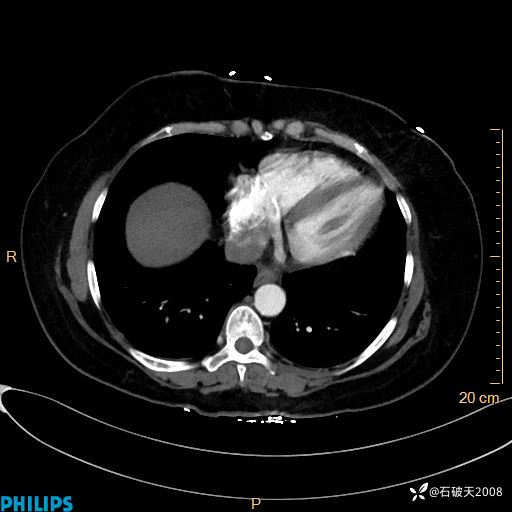

动脉期